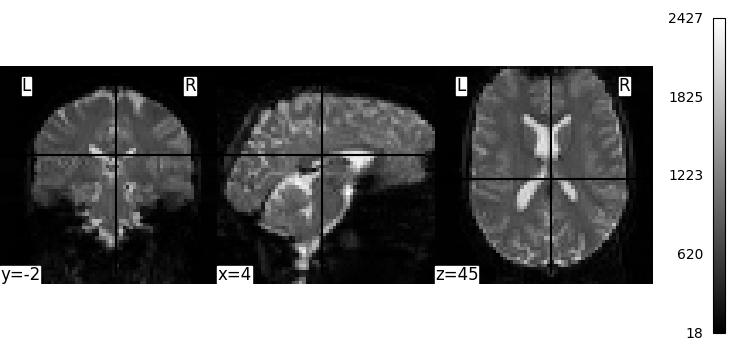

We can display the mean functional image and the subject’s anatomy:

plot_img(mean_img, cbar_tick_format="%i")

plot_anat(subject_data.anat, cbar_tick_format="%i")

show()